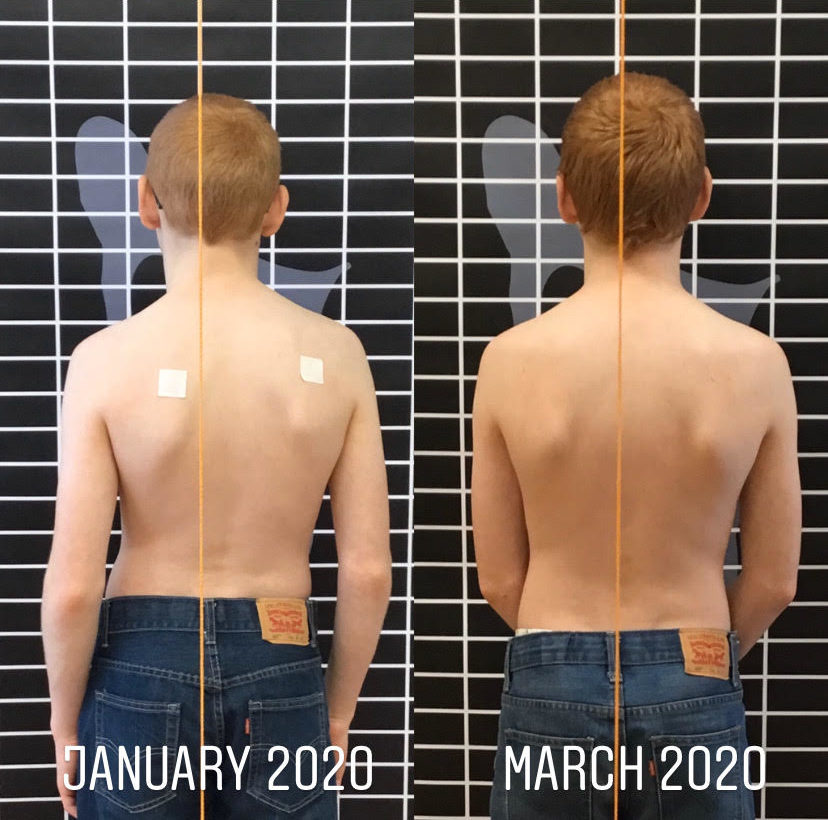

تقليل دوران الجذع (ATR): يقل التواء الجسم، ما يحسن مظهر الظهر عند النظر من الخلف.

دعم الصحة النفسية: رؤية تحسن في شكل الجسم وتقليل الانحناء يرفع الثقة بالنفس لدى المراهقين.

المتابعة الدورية: تصوير العمود الفقري كل فترة لتقييم التقدم.

ج: غالبًا بعد عدة أشهر من الالتزام بالتمارين المنتظمة، مع تقييم دوري للانحناء.